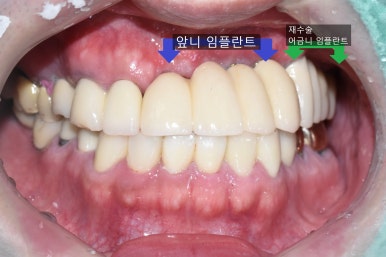

아래 사진의 환자분은 임플란트 주변 뼈가 녹아서

임플란트 픽스쳐부분이 뼈와 붙어있지 않아 흔들리는 상태였습니다.

처음 내원시

오래된 임플란트 2개를 제거하고

옆에 흔들리는 이까지 발치 한 후

재수술 임플란트는 2개를 심고 머리3개짜리를 완성하였습니다.